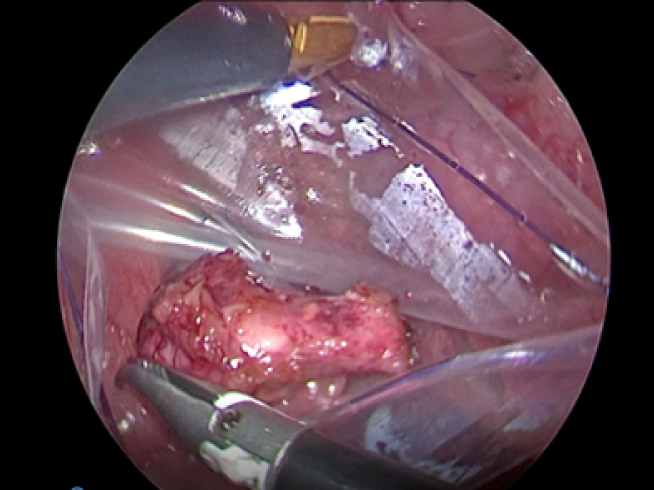

離断した副腎をバッグに入れて外へ出します。

出血もほとんどなくとても綺麗に摘出することが出来ました。 今回の手術時間は短く約45分でした。 病理検査の結果、副腎皮質癌という悪性腫瘍でした。 とても元気すぎてすぐに退院していきました。

実際の手術風景です。

↑実際に取り出した右副腎 (1.7×1.8cm)

犬の右副腎2.5cm。腹腔鏡下手術。3ポートで摘出が可能。